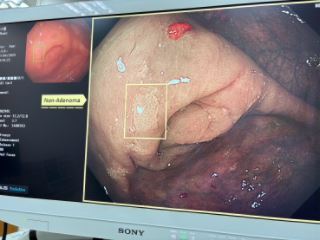

(1) AI 輔助內視鏡檢查系統:透過人工智慧協助即時辨識細微病灶與早期息肉,有效提升診斷精準度。整體大腸腺瘤偵測率顯著提升至35-40%,高於國際平均標準(25%)。研究顯示:每提升 1% 大腸腺瘤偵測率,可降低大腸癌發生率 3–5%。此技術顯著提高大腸癌早期診斷率逾 1.5 倍。

(3) 採用最先進頂級內視鏡系統:引進最新型主機與內視鏡系統,新一代特殊光全景對焦及放大功能,搭配4K螢幕影像輸出,可快速精準判斷檢查影像資訊。除提升腺瘤偵測率外,執行各項處置過程亦清晰準確,整體併發症比率小於千分之3,安全性遠優於國際標準(3%)。